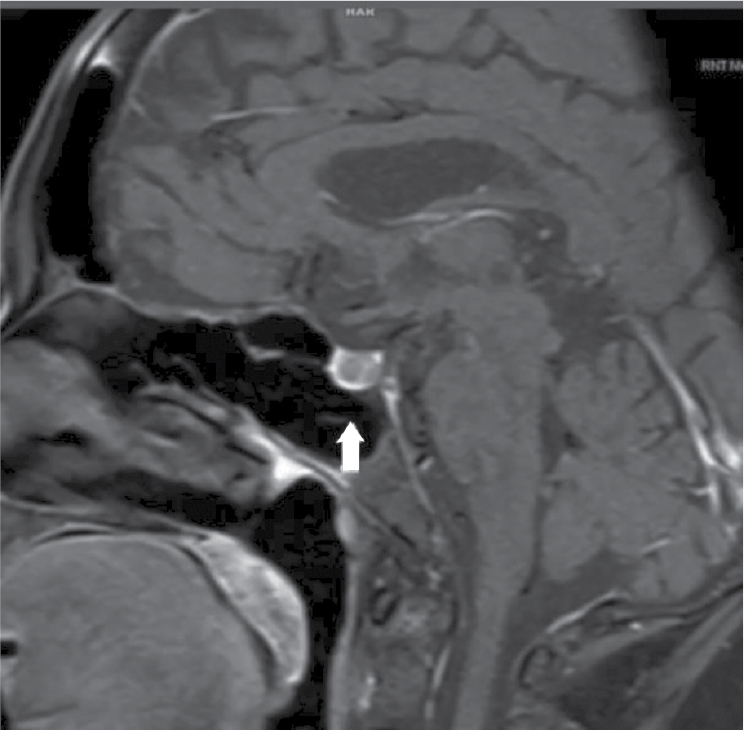

Magnetic resonance imaging (MRI) scan of the pituitary gland with contrast showed a hypointense lesion of size measuring approximately 6 ´ 5 mm is seen involving the right side of the pituitary gland. There is no extension above sella turcica suggestive of pituitary microadenoma (Fig. 4).

Figure 4. MRI pituitary with contrast showing hypointense lesion involving the right side of the pituitary gland. There is no significant enhancement in post-contrast. There is no extension above sella turcica suggestive of microadenoma.